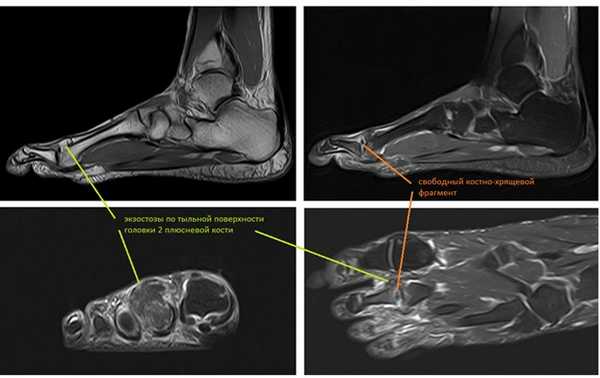

МРТ позволяет оценить мягкотканные структуры, на представленных ниже снимках видно как сухожилие разгибателя пальца буквально натянуто на огромныйостеофит выросший по тыльной поверхности головки 2 плюсневой кости.